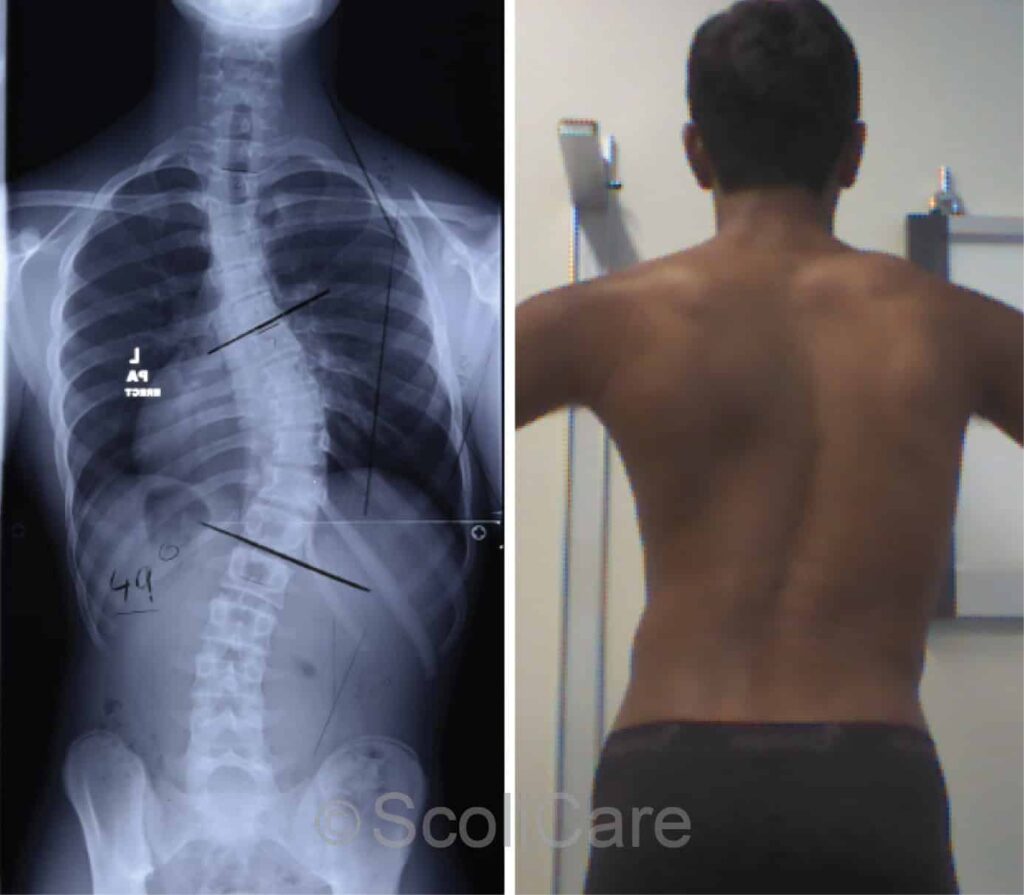

Scoliosis is a spinal deformity where the spine curves abnormally to the side, often forming an “S” or “C” shape. This curvature can occur in children, adolescents, or adults and may cause visible unevenness in shoulders or hips, back pain, and in severe cases, breathing difficulties due to rib cage distortion.

When the spinal curvature progresses beyond 45–50 degrees or begins to impact daily life, Dr. Nikhil Arbatti may recommend surgery. As one of the best spine surgeons in Mumbai, he specializes in minimally invasive spine surgeries that ensure precision correction, faster recovery, and minimal scarring.

Surgery is usually advised when the curvature is severe (above 45–50 degrees) or affects daily function and posture.